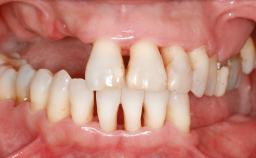

Ridge Preservation and Implant Placement for a Fixed Dental Prosthesis After a Car Accident

It is well known to clinicians that any removal of teeth will, over time, cause the dimensions of the alveolar ridge to be reduced by resorption of the bundle bone and by changes related to external modeling. This development is particularly evident in the crestal region with its thin buccal bone that consists of bundle bone almost entirely. The facial bone will rapidly resorb as blood supply from the periodontal ligament gets disrupted (Araújo and Lindhe 2005). There is no reason why traumatic tooth loss should not have the same consequences. It takes more than achieving implant osseointegration for a treatment outcome to be considered successful. No deficiency of bone or soft tissue is acceptable when an ideal esthetic outcome is the goal. Several articles (Sanz and coworkers 2011; Vignoletti and coworkers 2011) have reported on techniques of improving the alveolar ridge for implant treatment, notably focusing on protecting tissues from resorption.

Case Type Extended Space

# of Teeth 6

# of Implants 4